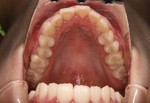

又、指を強く吸うタイプでは頬の筋肉が収縮することで上顎の横側の歯が内側に倒れて歯列がV字型になり、出っ歯や交叉咬合(下の奥歯のほうが上の奥歯より外側になって噛む状態)になることがあります(写真1、2)。

写真1 V字歯列